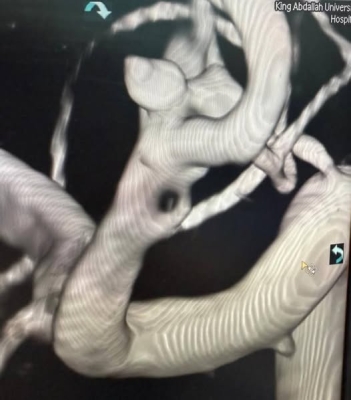

خبرني - تمكّن فريق طبي متخصص في مستشفى الملك المؤسس عبدالله الجامعي من إنقاذ حياة مريض يبلغ من العمر 57 عامًا، كان يعاني من نزيف دماغي حاد ناتج عن انفجار أمّ الدم في الشريان السباتي الداخلي وتفرع الشريان الدماغي الأمامي مع الأوسط .

وخلال العملية، تم تركيب شبكة دقيقة بين الشريان الدماغي الأوسط والشريان السباتي الداخلي، ما ساعد على تحويل مسار الدم بعيدًا عن الكيس الدموي المنفجر، وبالتالي وقف النزيف بشكل كامل .